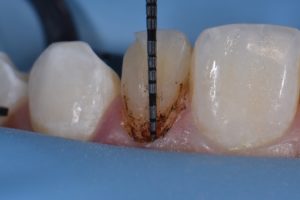

This case was referred to me for improvement of the esthetics of composite bonding on #7 and 10. A diagnostic wax-up was generated as the referring dentist required certain proportions relative to primary anatomy to be confirmed before starting. A decision was made to modify the gingival contour of 10 (diode, 810nm, 980nm, 1.0W SuperPulsed) (Gemini, Ultradent, UT), with bone sounding the basis for whether osseous recontouring was necessary. In this case, transsulcular osseous recontouring using a Wedelstaedt chisel (Kois) (Brasseler) was utilized to re-establish biologic width on the day of the restorations. Approximate full healing time: 3 months. Approximate “purple” look to gingiva: 2-3 weeks. Most of the old composite was removed except for areas where it could not easily be distinguished from tooth structure. After defining finish lines, the teeth were isolated with metal strips and micro air abraded (27 micron aluminum oxide) before a total etch approach. Silane coupling agent was utilized (GC G-MultiPrimer) before bonding (GC G-Premio Bond). A layered approach was utilized (4 separate layers) using shades XL1 Enamel, A1 Enamel, XL2 Dentin, Trans Clear from Kerr Harmonize.